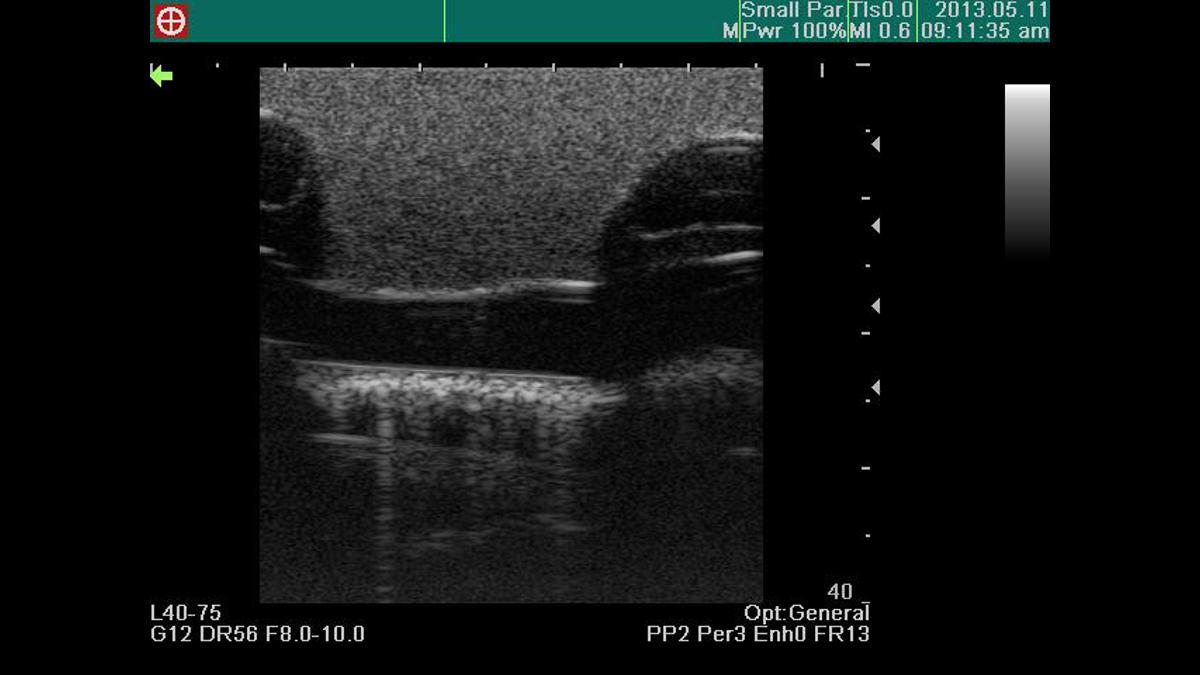

Excellent ultrasound image

Confirmation of ventricles, ribs, pericardium, liver and main artery under ultrasound scanning

Recognition of anatomical landmarks using ultrasound

Visualization of pericardial fluid using ultrasound scanning